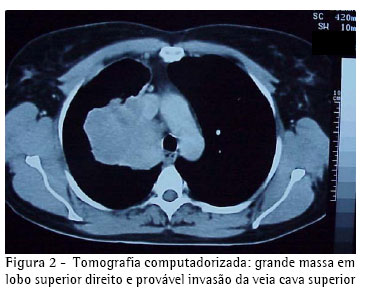

Pela suspeita tomográfica de invasão da veia cava superior e veia ázigos, a investigação prosseguiu através de uma cavografia, que não evidenciou comprometimento destas estruturas (Figura 3).